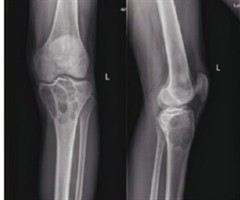

胫骨近端骨巨细胞瘤合并动脉瘤样骨囊肿1例并文献复习

中图分类号:R738.1 文献标志码:B DOI:10.3969/j.issn.1003-1383.2025.12.014 骨巨细胞瘤(giantcell tumorofbone,GCT)为低度恶性或潜在恶性的肿瘤,由Jaffe于1940年...